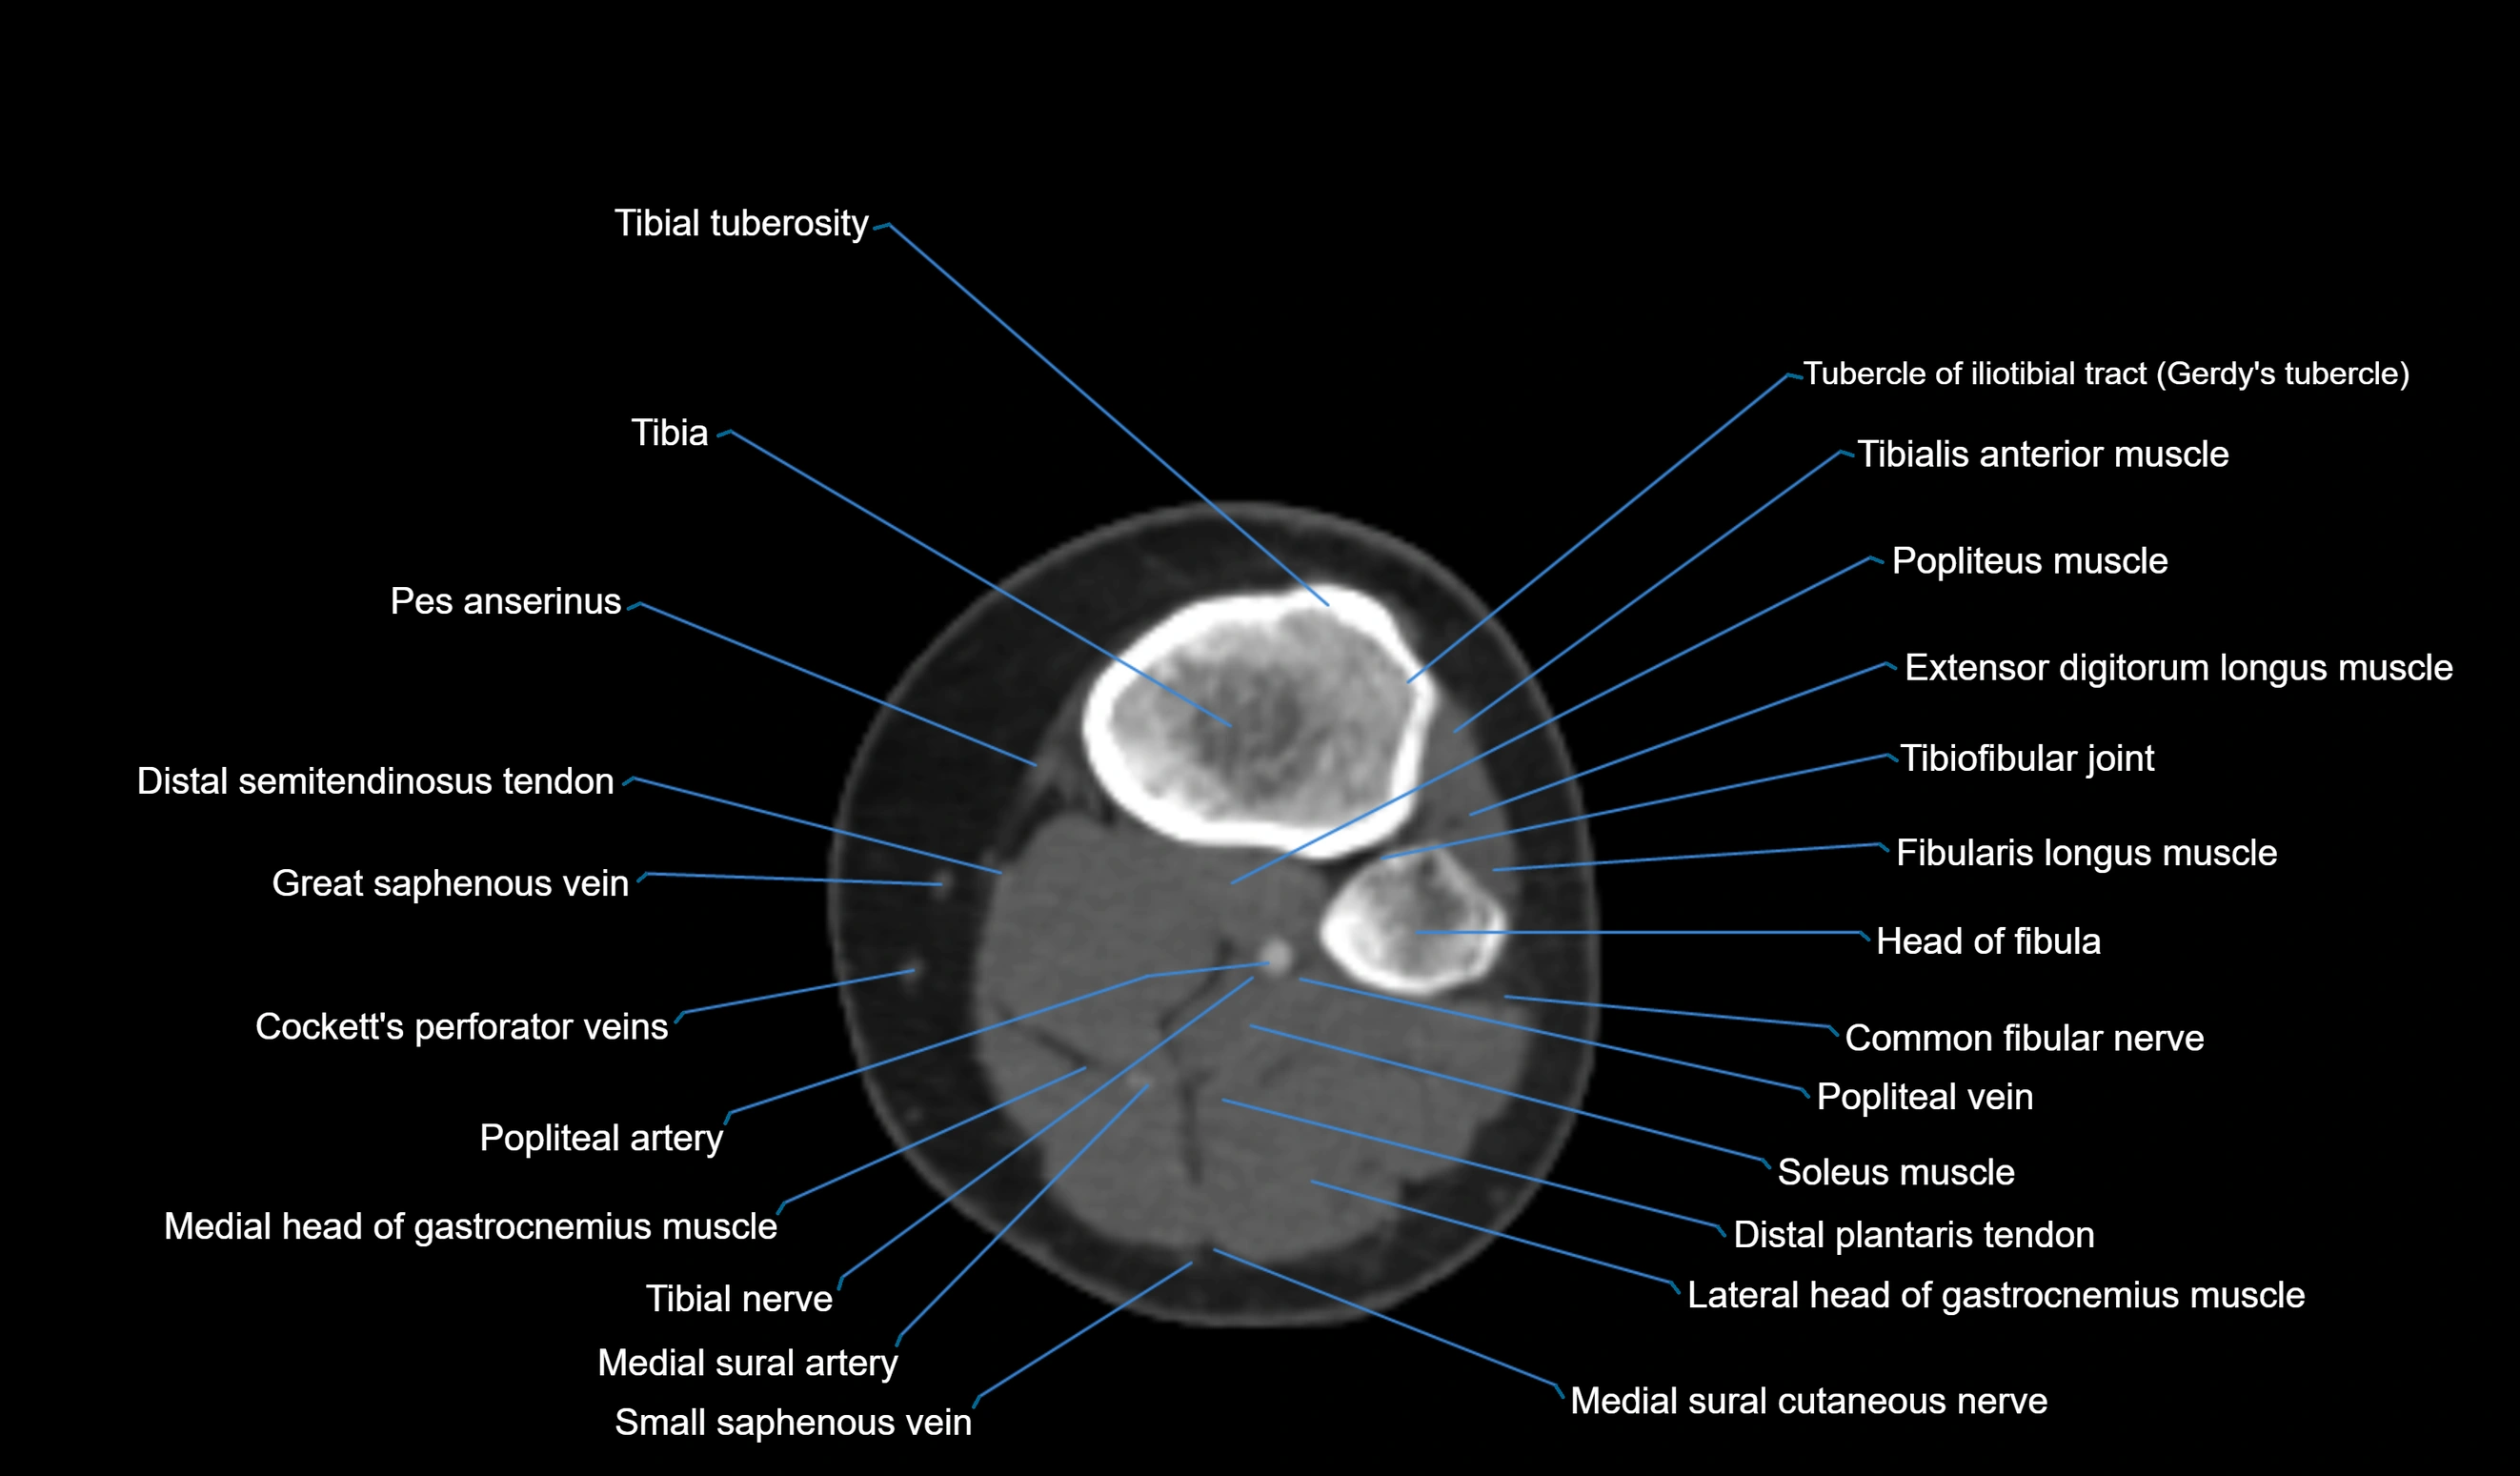

CT VRT 3D image

CT image